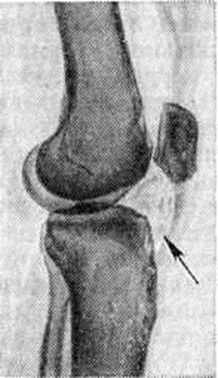

Клиническая картина весьма характерна. Больного беспокоят боли в суставе, «хруст» при движениях, пальпация сустава болезненна в области собственной связки надколенника; определяется выпот в суставе; при разгибании голени характерно выбухание двух валиков по обе стороны собственной связки надколенника, движения в суставе ограничены, особенно при сгибании. На артропневмограмме склерозированные жировые складки видны в виде плотного ячеистого треугольника (рисунок). Постановку диагноза облегчает наличие типичных анамнестических данных (длительная травма сустава или перегрузка его однообразными движениями).